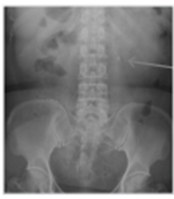

1.5cm 미만이면서 임신 가능성이 없고 출혈성경향이 없어야 하며 distal ureter나 UPJ obstruction이 없어야 한다. 최근에는 nonenhanced CT가 진단적 도구로 많이 활용되므로 warfarin 등을 복용하지 않는 환자에서 aortic dissection이 없다는 것을 image에서 알 수 있다. 이러한 환자에서는 distal ureter stone이 없다는 전제하에 renal stone에 대한 ESWL을 시행할 수 있다. 사진은 renal stone에 대한 ESWL 후 추적관찰에서 파쇄된 stone들이 proximal, distal ureter로 이동하는 모습을 보여준다.

<figure-inline>전공의핸드북 그림2.png</figure-inline>